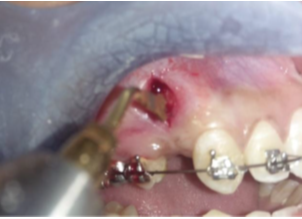

Following procedure was used for piezocision:Piezocision was performed by making a single vertical incision distal to canine, starting 3mm apical to marginal gingiva to preserve gingival papilla and extending 10 mm apically, using a 15 no blade with BP blade handle. Piezotome (Dmetec, Korea) was used to make cortical cuts of 3mm depth in entire length of incision as shown in ([Figure 5])

In our study also Piezocision ([Figure 5], [Figure 6]) was performed similar to the procedure described above. The soft tissue incision was made starting 3mm away from marginal gingiva. The sparing of marginal gingiva and associated bone from surgical trauma was done to prevent alveolar bone loss and gingival recession as has been described by Abbas et al.[3], Sebaoun et al.[25] and Hoogeveen et al.[26] The piezocision cuts extended 10mm in length distal to canine